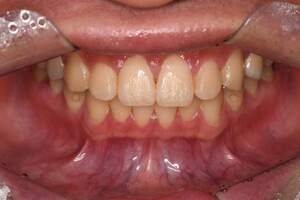

歯石除去

治療前

治療後

| 年齢 | 32歳・男性 |

| 主訴 | 全顎クリーニング |

| 治療内容 | 歯石除去 |

| 治療期間 | 60分×2回 |

| 費用 | 合計5,000円 初診料3,000〜4,000円前後 歯石除去約1,000円(2022年6月現在) |

| リスク・副作用 | ・処置後に歯がしみることがあります。 ・歯肉の炎症がある場合は歯石除去中に出血を伴う可能性があります。 ・歯ぐきの炎症が軽減すると歯ぐきが引き締まり、歯が長く見えることがあります。 |